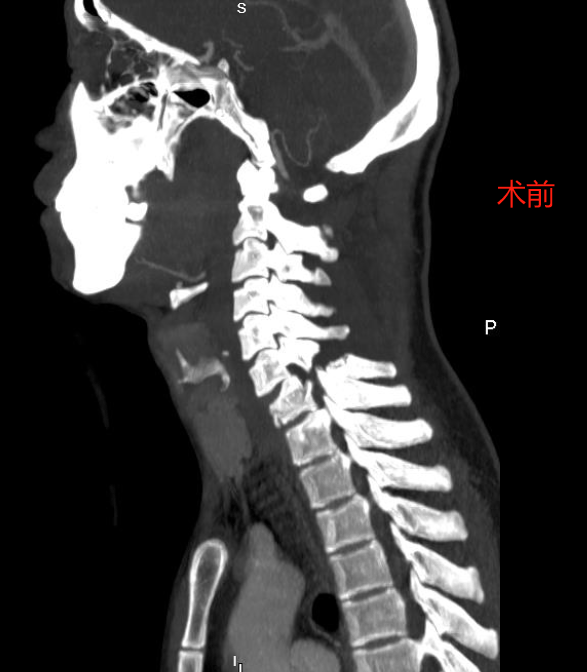

脊柱外科收治一例因车祸伤导致非骨折脱位型颈部脊髓损伤并高位截

车祸致第二颈椎骨折,精湛医术救治助其平安脱险